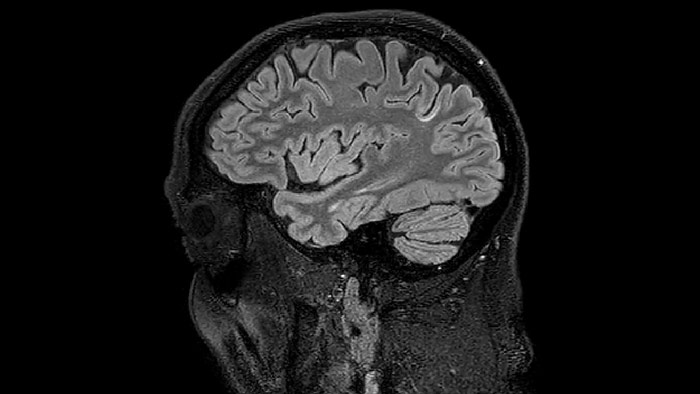

QSM elition Kames algorithm

QSM based on a Compressed SENSE multi-echo SWI.